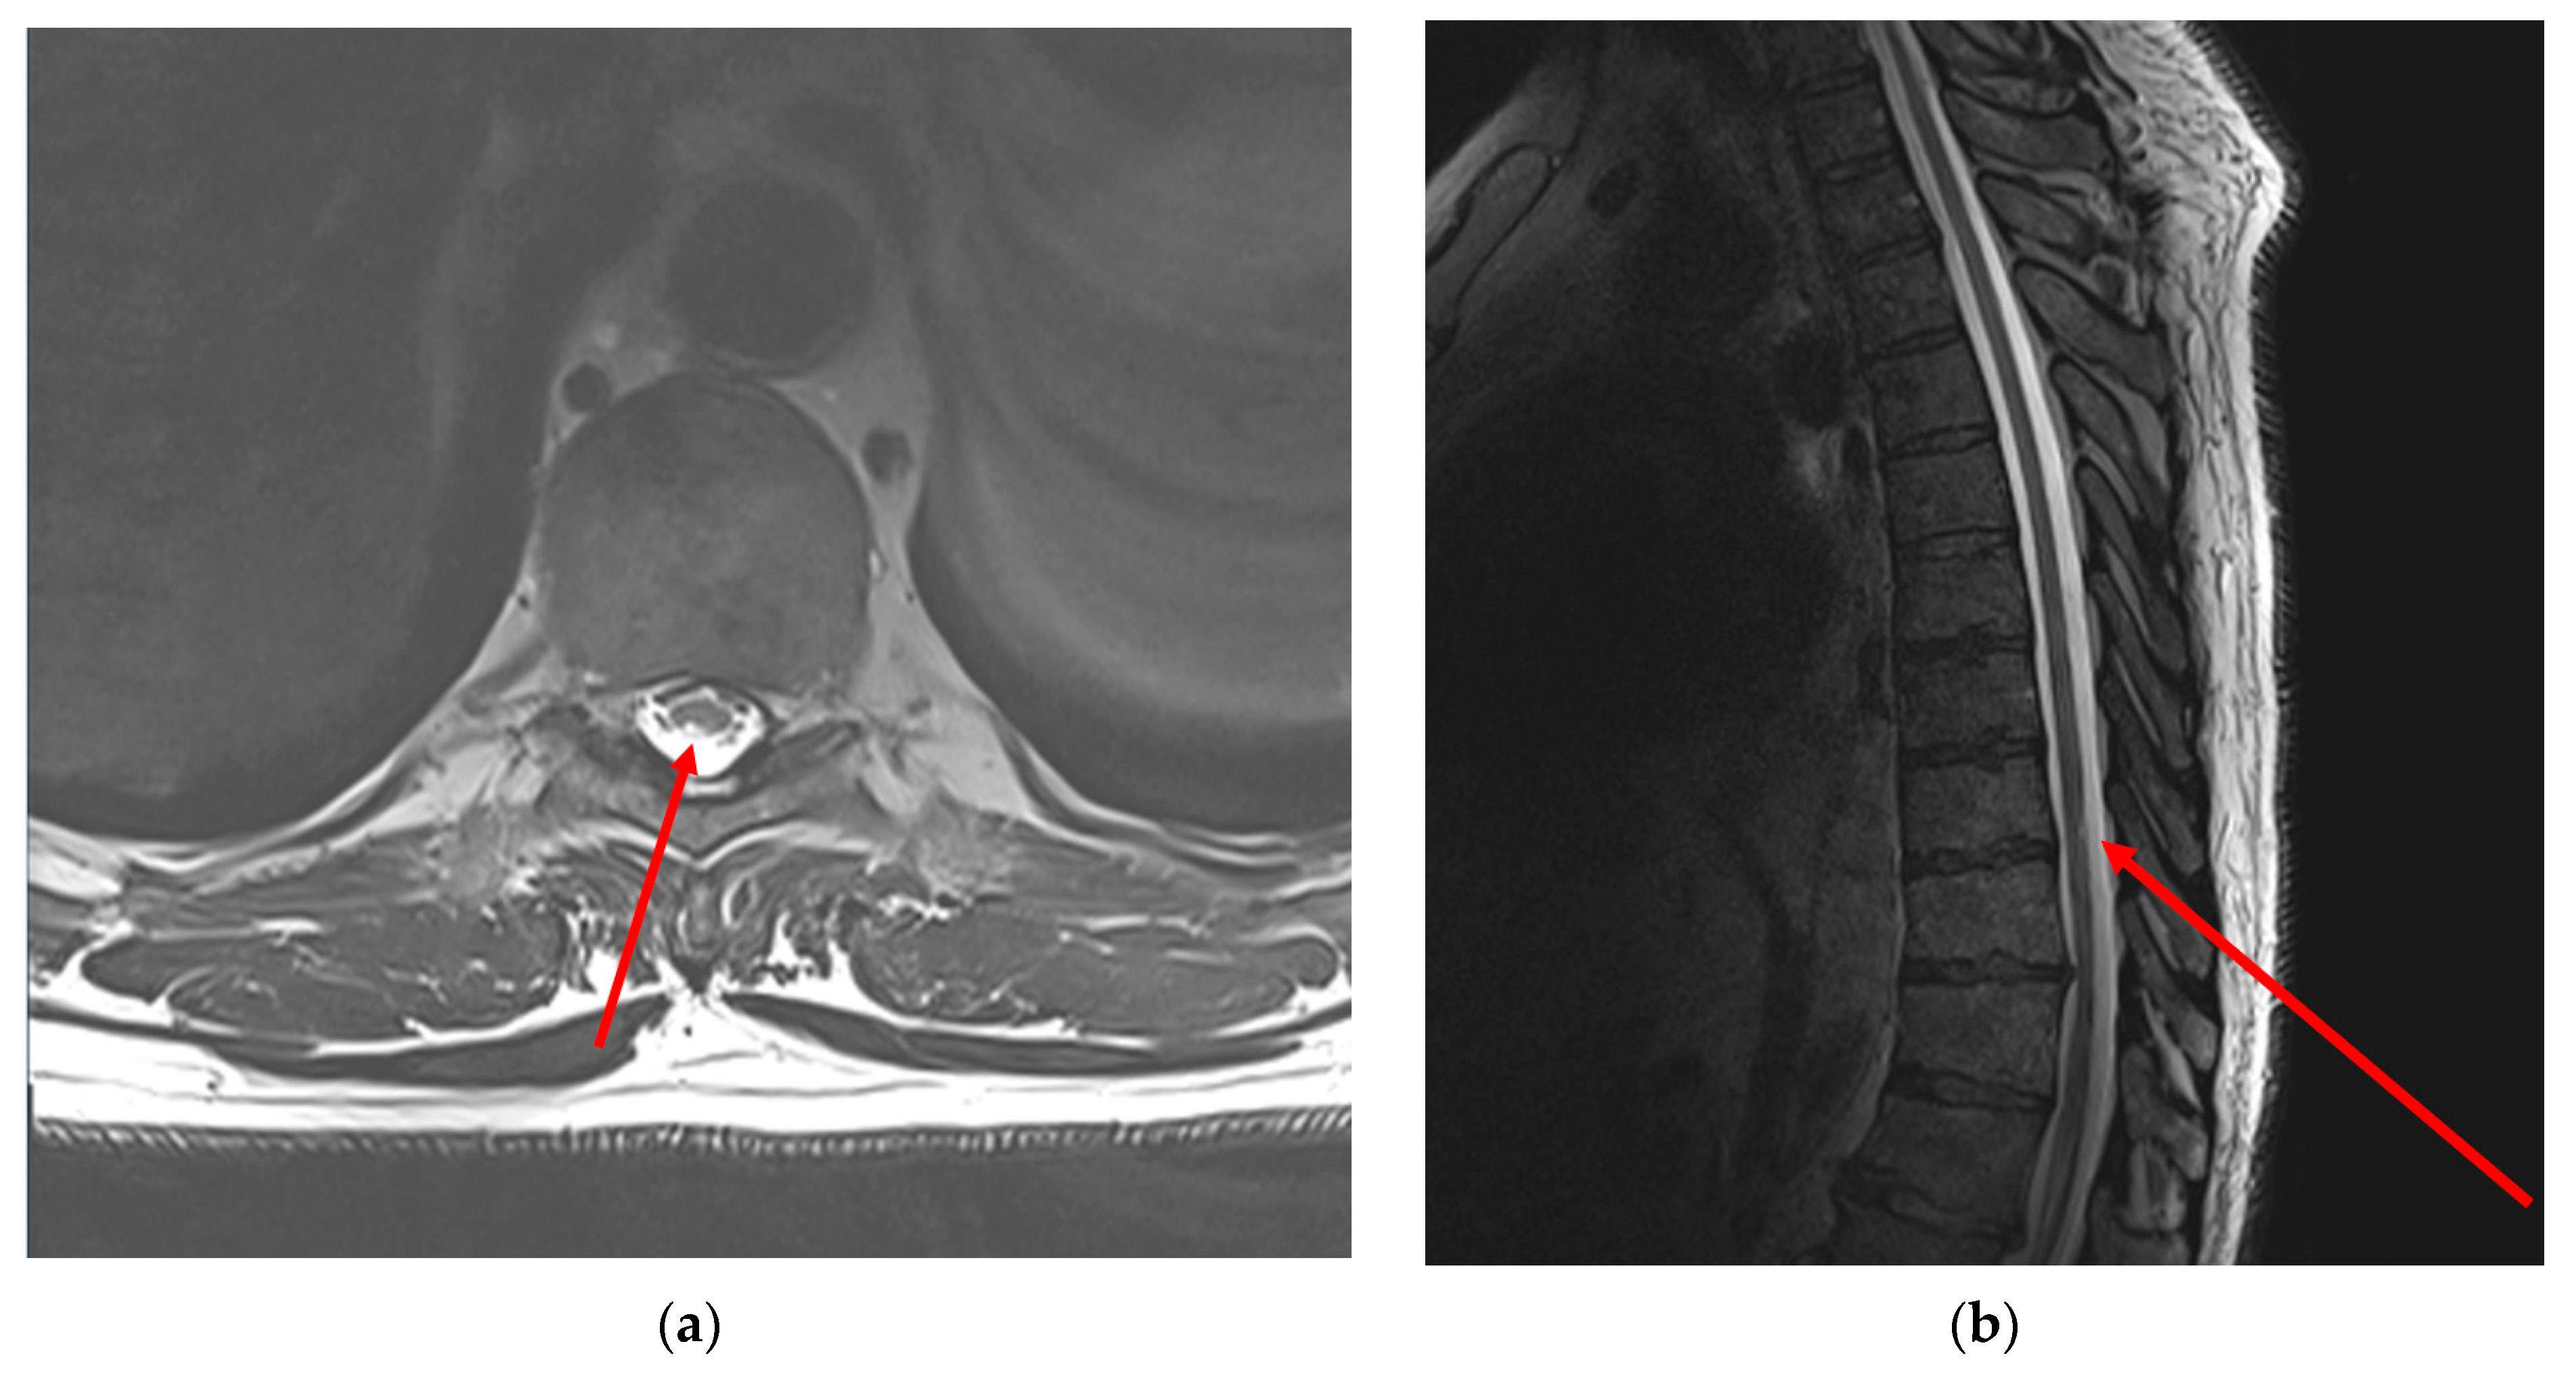

- Thoracic MRI: T2-weighted MRI images of the thoracic spine showed asymmetrical mild patchy high-signal changes in the spinal cord between levels D9 and D10, affecting the posterolateral sides of the spinal cord bilaterally, but predominantly on the right side with minimal swelling (Figure 1).